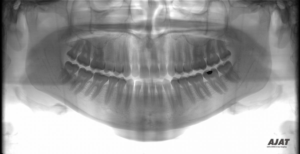

I naše ordinace nabízí vysoce kvalitní panoramatický rentgen, osvědčený model Ajat ART Plus. Tento přístroj díky své multifokální technologii a vysoce kvalitnímu CdTe senzoru umožňuje zhotovit OPG snímky s unikátním rozlišením. Patří mezi rentgeny na trhu, které kombinují CdTe-CMOS technologii (revoluční patentovaná technologie s přímou konverzí rtg záření na elektrický signál, výsledkem je: 3x vyšší citlivost senzoru, 3x lepší kvalita zobrazení, vysoký dynamický rozsah snímku) s technologií multifokální. Panoramatický snímek je tedy s 3x krát lepší kvalitou než u mnohých jiných panoramatických rentgenů navíc s možností posunu fokální vrstvy po projekci s přesným zaostřením na všechny úseky maxilárního a mandibulární oblouku. Výsledkem je vyjímečně ostrý snímek ve všech úsecích.

zdroj: ajat.fi